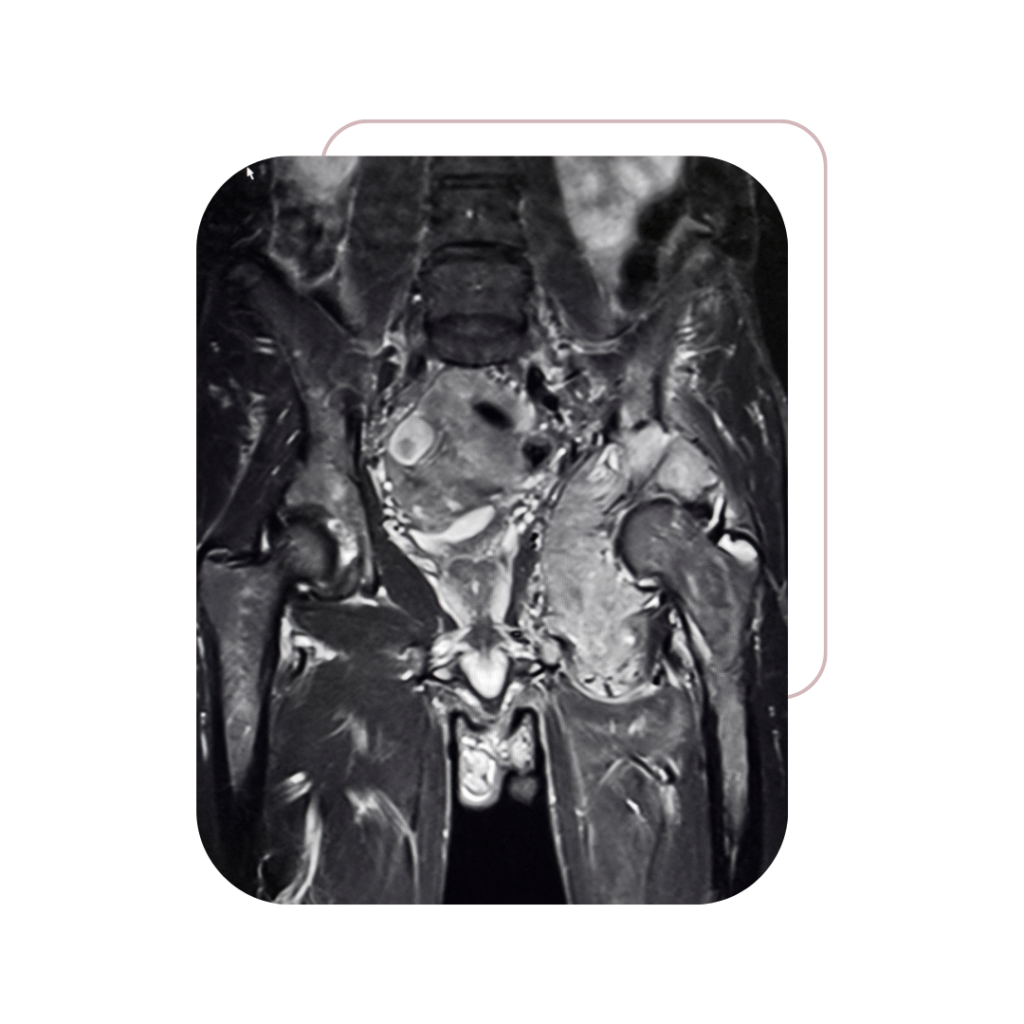

A Dra. Jacqueline Menezes dedica sua carreira ao tratamento e à preservação da saúde da mulher, com foco em cirurgias oncológicas ginecológicas seguras e minimamente invasivas.

Ginecológicos

Massas Pélvicas

e Abdominais